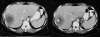

We report a new case of a brucellar liver abscess (brucelloma) in a young woman without previous remote brucellosis who presented with pronounced systemic and mild local symptoms. Brucelloma is the result of calcification of a granoulomatous reaction induced by persistent Brucella in macrophages. It represents a rare manifestation that follows previously undetected brucellosis. We describe the findings in plain radiograph, ultrasound, computed tomography, and magnetic resonance images. Together with the positive serology, imaging yielded important elements supporting the diagnosis. Modern radiological techniques also contributed to the final therapeutic management, preventing unnecessary laparotomy. Sequencing confirmed the definite diagnosis of Brucella melitensis as the causative factor.